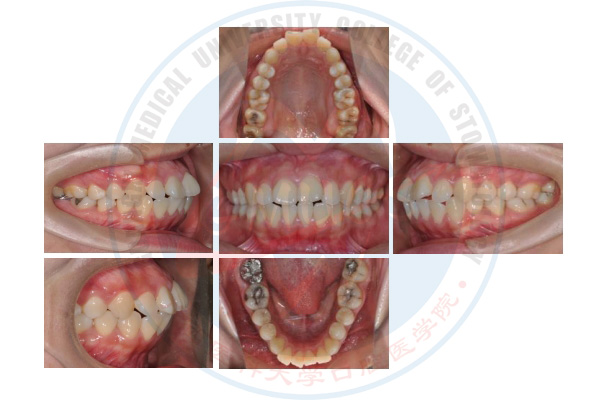

舌侧个性化矫治技术

正畸治疗前

正畸治疗中

正畸治疗后